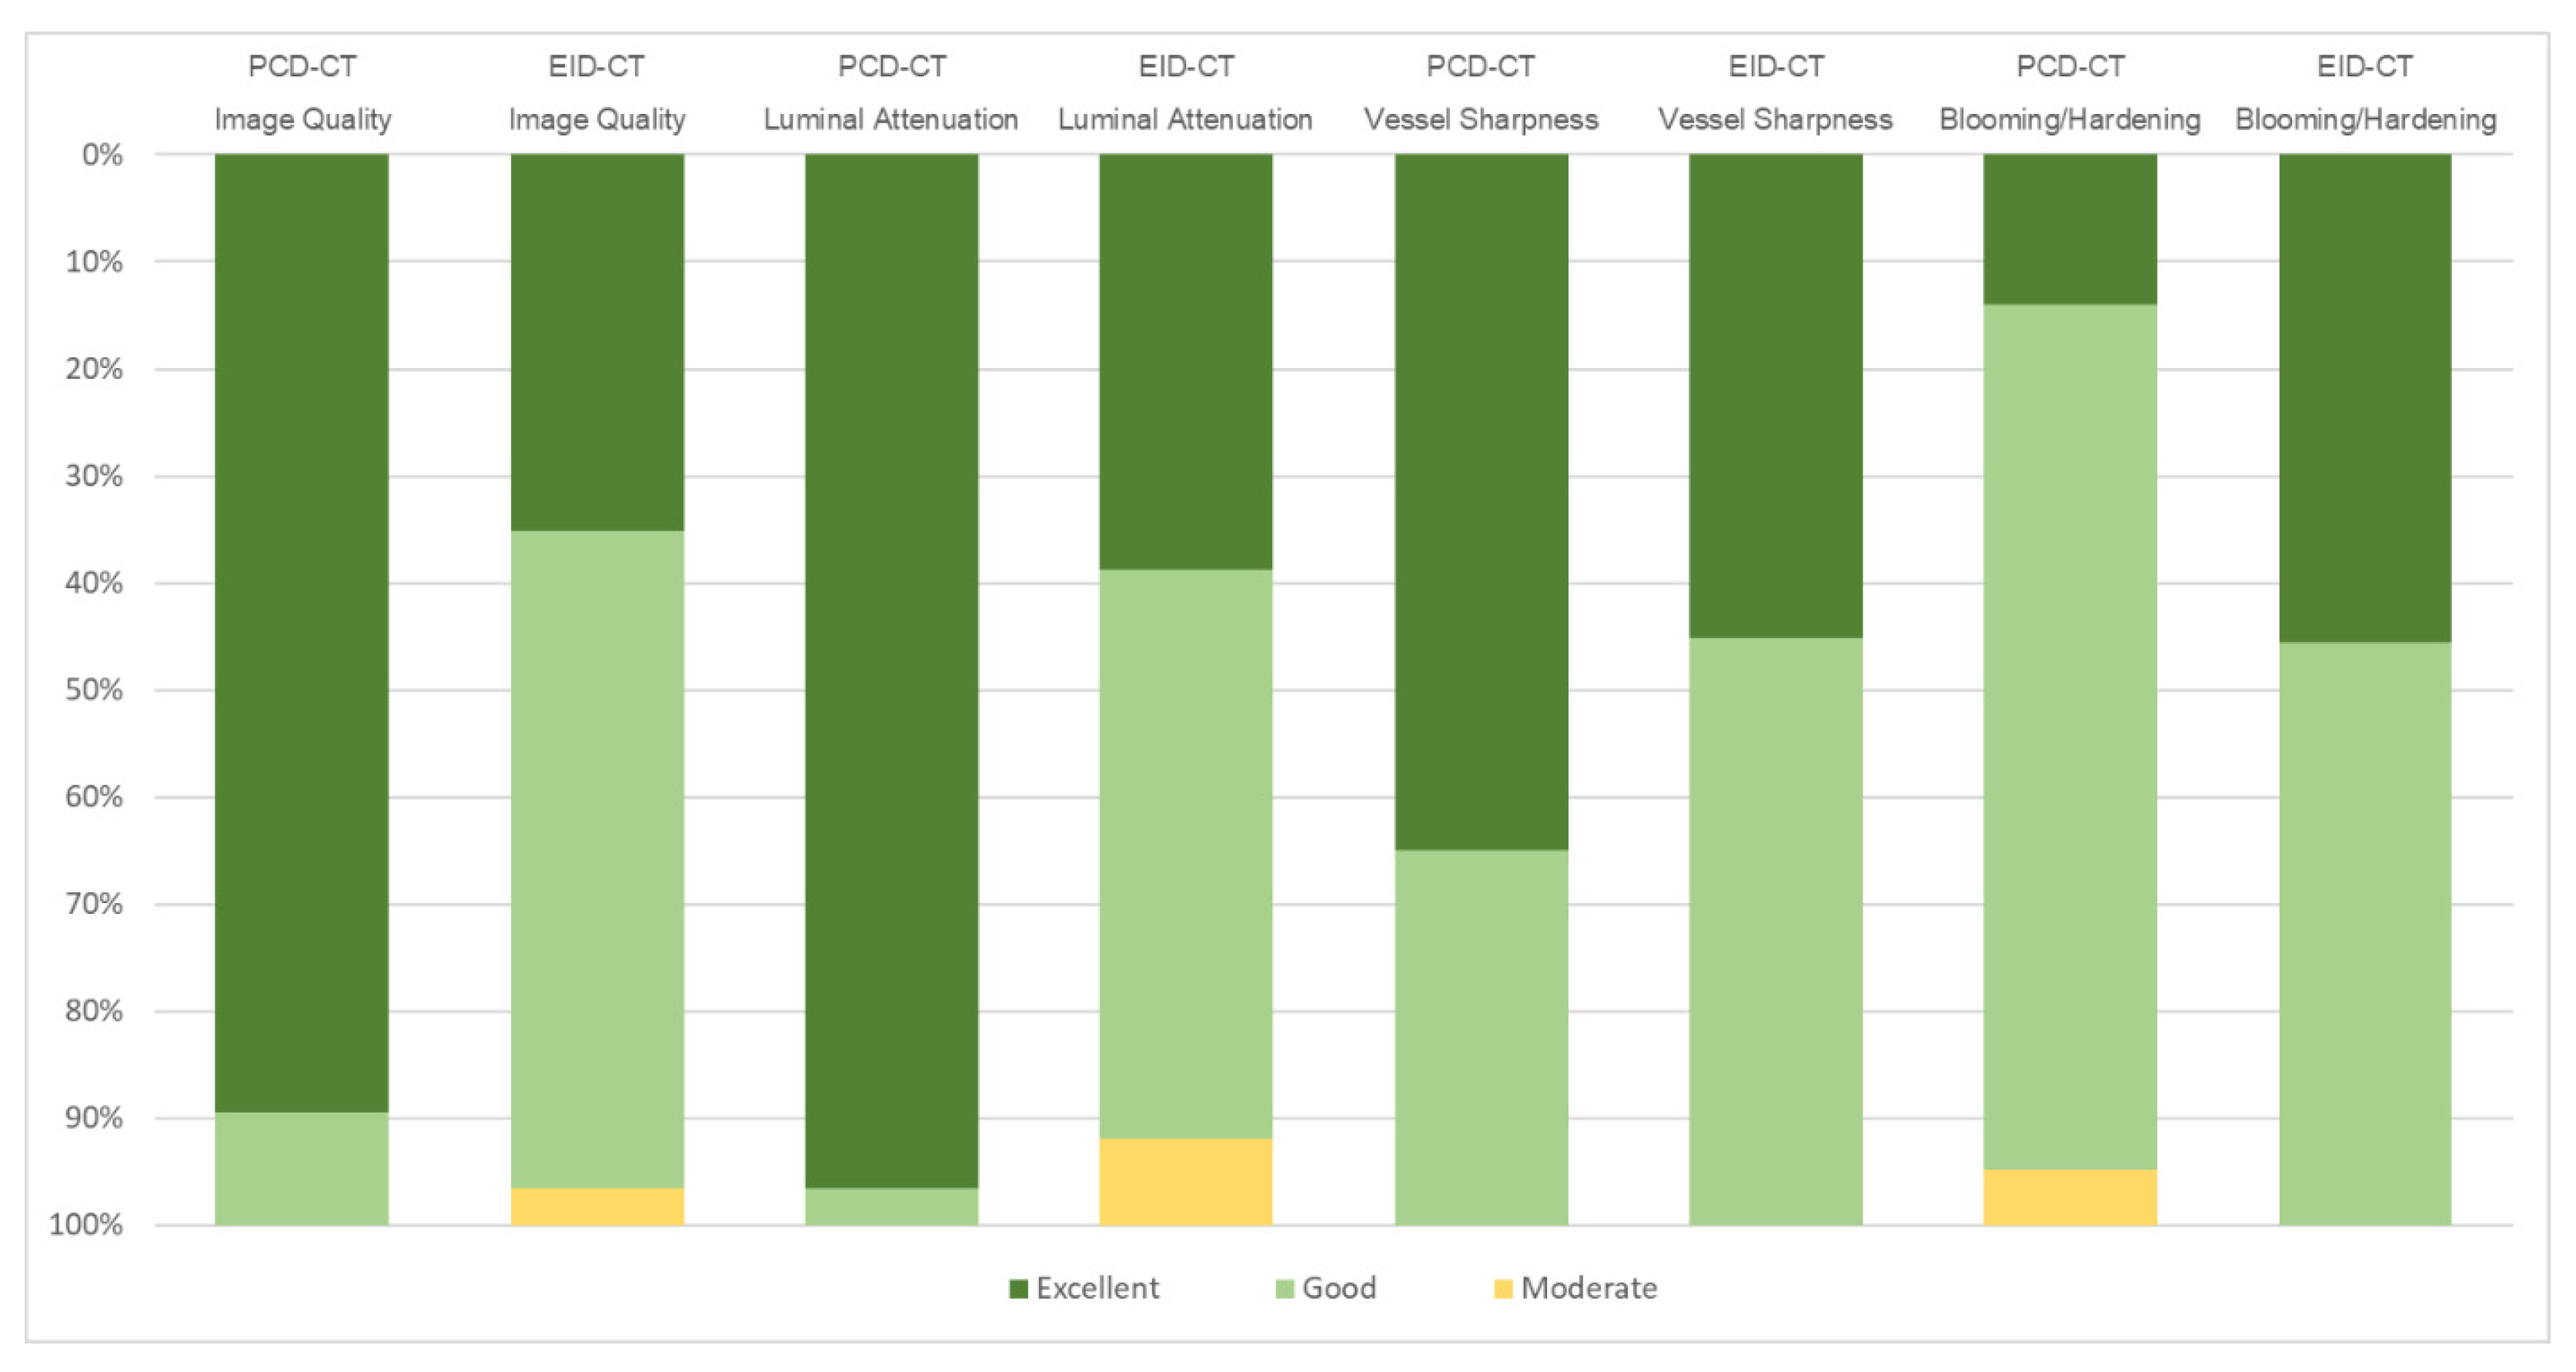

3.3. Subjective Image Quality